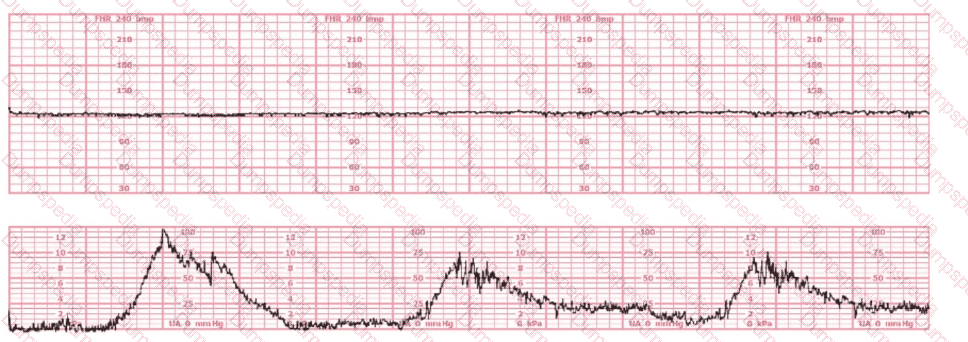

The tracing shown is from a woman at 28-weeks gestation in the post-anesthesia care unit (PACU) after an appendectomy. She is alert and awake. Based on this fetal heart rate pattern, the most appropriate intervention is: